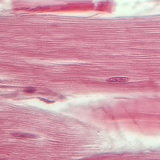

800-fold magnification

Biology